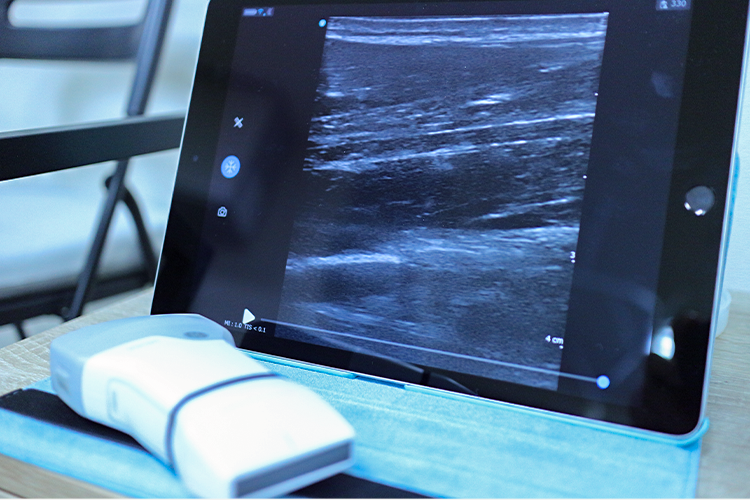

その一方で、ハイボルテージ(高電圧)治療器や立体動体波、衝撃波治療器など、従来の低周波治療器と比べてはるかに高い治療効果が望める、最新の物理療法機器を積極的に導入し、いかなる症状に対しても最適な治療を提供できる体制を整えております。

また、も備えているため、骨や関節の細かな状態や、靭帯・筋肉・腱・神経・血管などの軟部組織の状態を観察できます。

これにより患部の場所や状態を正確に把握し、適切にアプローチすることができます。